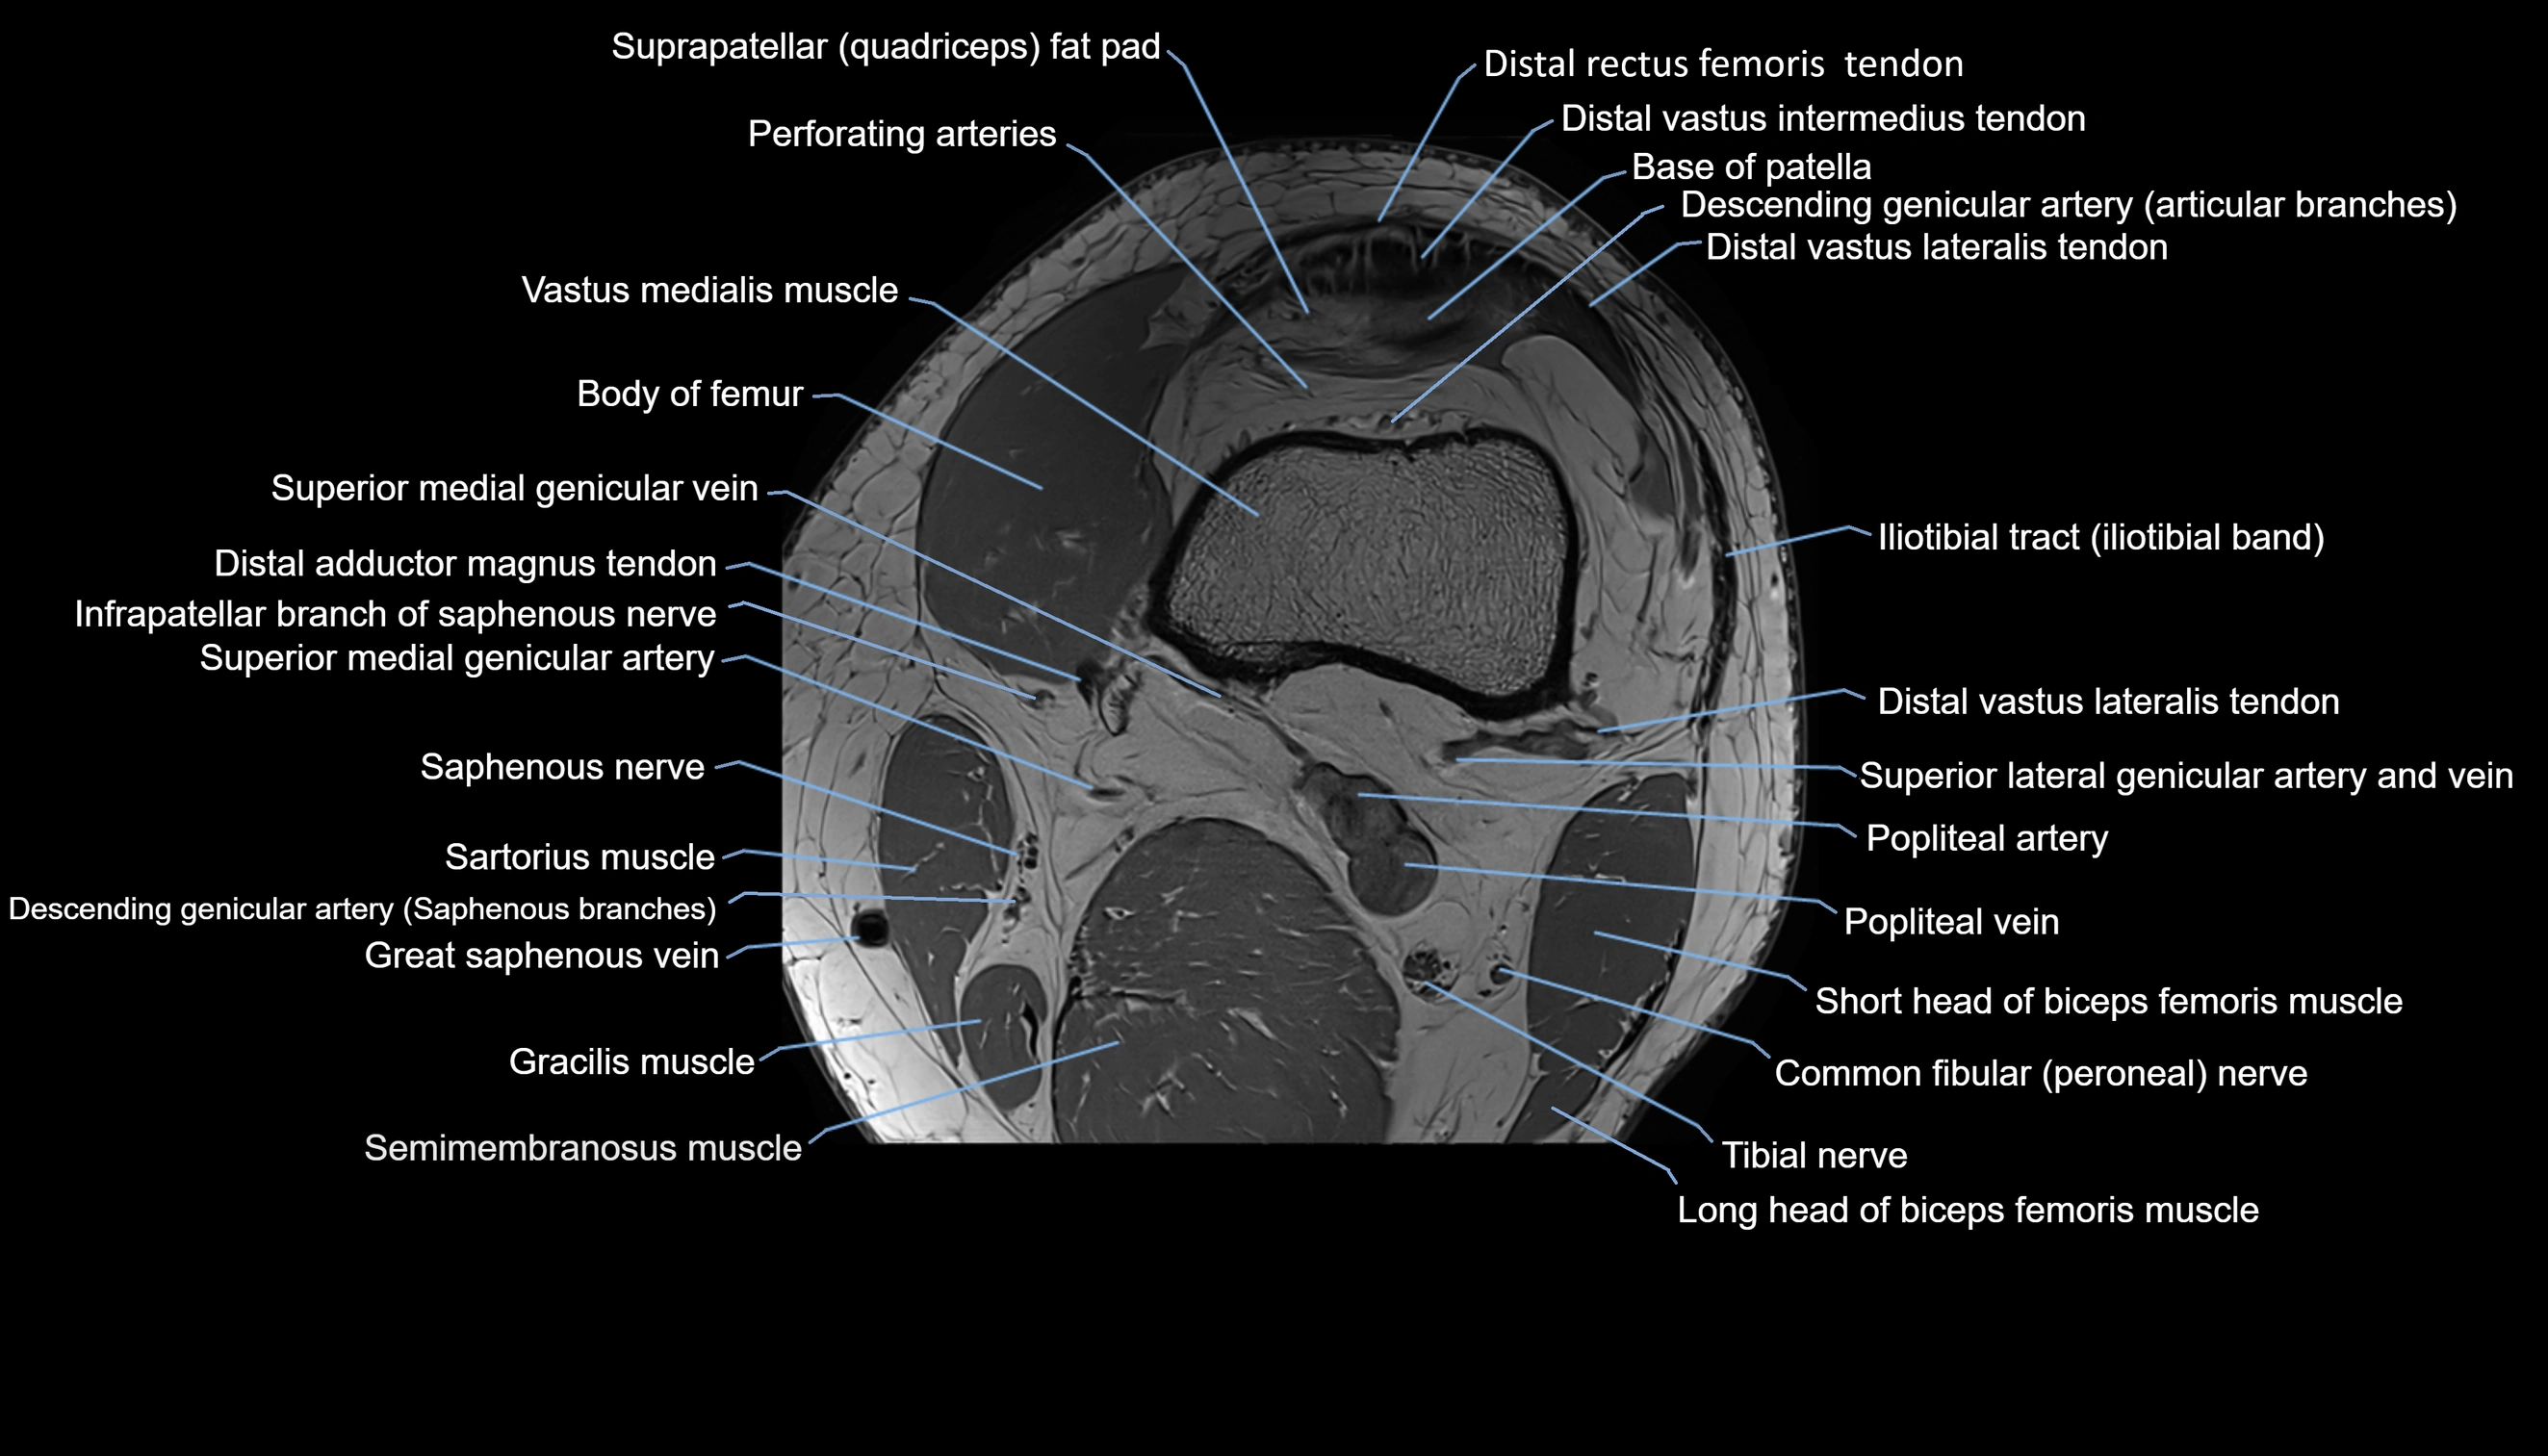

- Body of femur

- Perforating Arteries (Knee joint)

- Popliteal artery

- Popliteal vein

- Saphenous nerve

- Sartorius muscle

- Semimembranosus muscle

- Tibial nerve

- Vastus lateralis muscle

- Vastus medialis muscle

- great saphenous vein